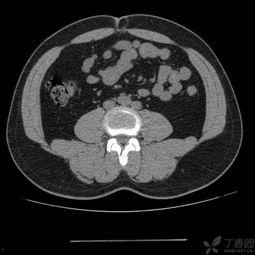

首先,得先弄清楚什么是脐疝。脐疝,顾名思义,就是发生在肚脐部位的疝气。它通常是由于腹壁肌肉薄弱,导致腹腔内的器官(如小肠、大网膜等)通过这个薄弱点突出到体外形成的。成人脐疝,就是成年人得的这种疝气。